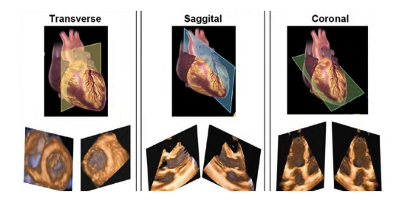

Hình 2: Siêu âm tim 3D real-time

- Tim được quan sát theo 3 mặt phẳng: mặt phẳng đứng ngang (transverse), mặt phẳng đứng dọc (saggital), mặt phẳng nằm ngang (coronal).